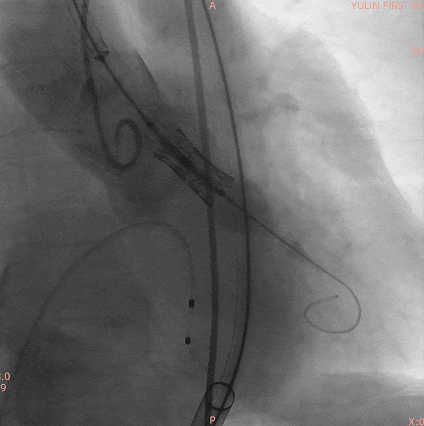

手术过程

通过术前精准评估,患者在全麻下行TAVR手术,DSA和食道超声双重引导,通过穿刺心尖建立工作路径,沿加硬导丝送入19mm*40mm球囊预扩张主动脉瓣,球囊无腰有漏,利用短鞘送入25#RENATUS瓣膜至左室,猪尾巴导管再次造影确认位置。将25#RENATUS瓣膜顺利跨瓣,精准定位,5ATM精确释放,退出输送系统再次行主动脉根部造影,示瓣膜膨胀充分,无瓣口反流,无瓣周漏,冠脉血流正常,术后即刻平均跨瓣压差降至3.62mmHg,超声示术后峰值流速降至0.95m/s。瓣膜释放位置理想、形态及功能良好,瓣叶启闭良好,无外周血管损伤。

术中影像

25#Renatus瓣膜造影定位

快速起搏下5atm精准球扩释放25#Renatus瓣膜

释放后造影示瓣膜位置理想,形态良好